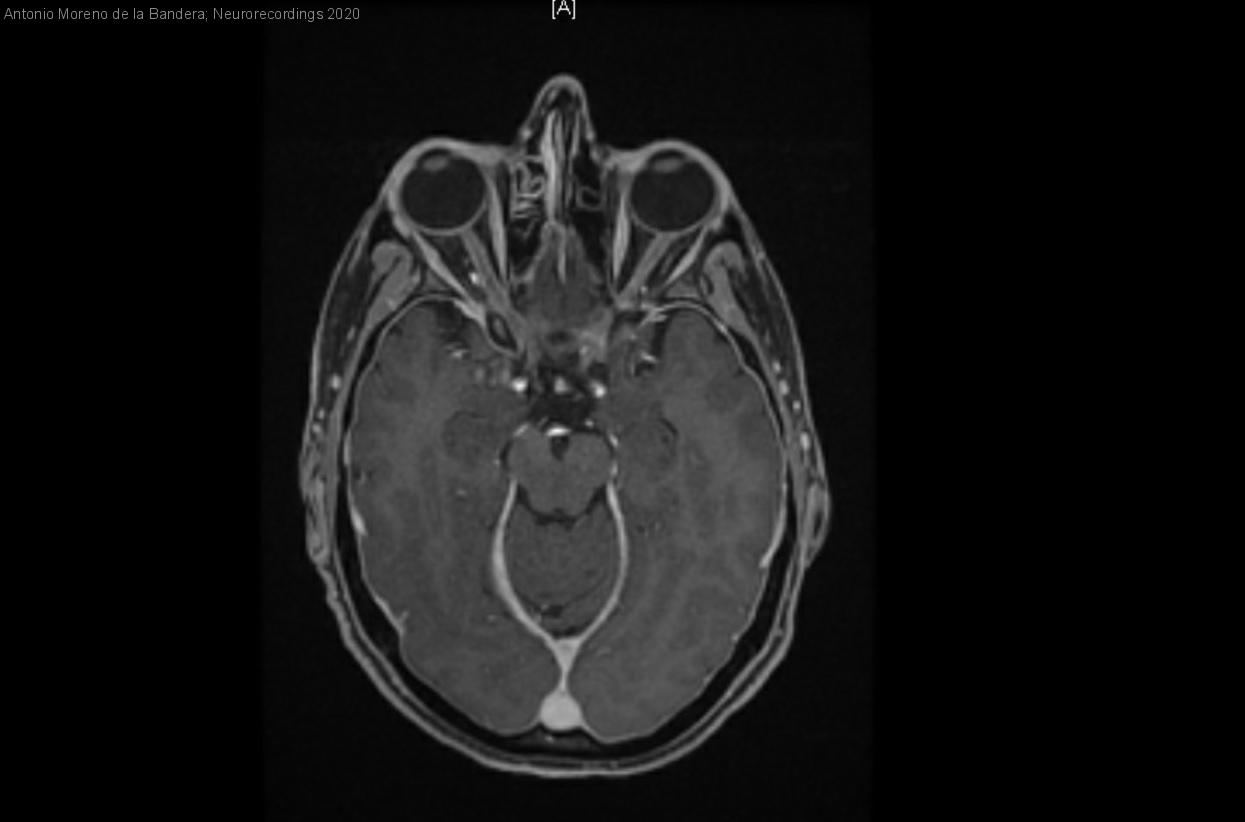

Mujer | 42 años

Diagnóstico final: Hipotensión intracraneal espontánea

Resumen del caso

Mujer de 42 años deportista con antecedentes de migraña episódica y neumotórax espontáneo. Anticonceptivos orales como tratamiento habitual. Acude a urgencias por cefalea holocraneal, opresiva, de instauración progresiva en pocas horas, alcanzando una intensidad máxima de 9/10 en la...